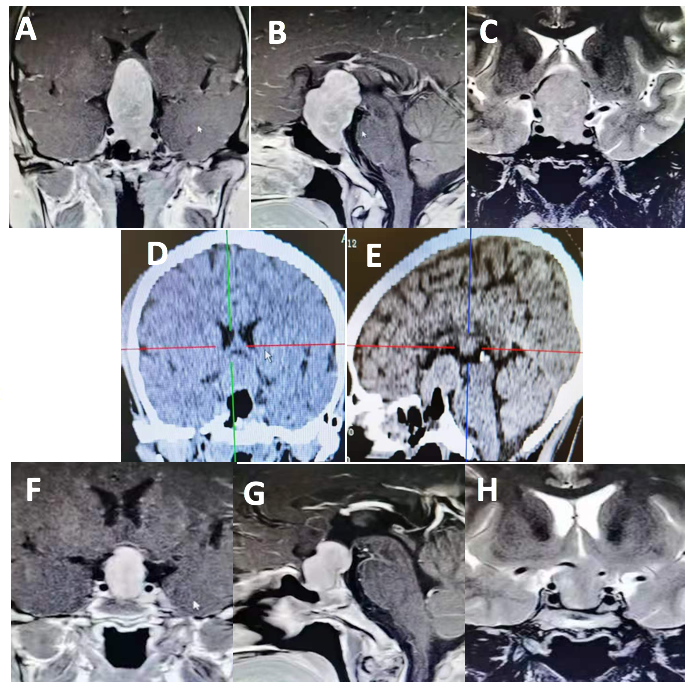

术后病理回报:垂体腺瘤。结合免疫组化及特殊染色结果,符合促性腺激素细胞腺瘤。免疫组化结果:ACTH-,Prolactin-,GH-,FSH-,LH+,TSH-,ER -,PIT -1+,SF-1+,T-PIT-,SSTR2-,P53-,Ki-67 1%+,Syn+。特殊染色结果:PAS-,网状纤维染色,网状纤维破坏(图3)。

图3. 术后病理:垂体腺瘤。